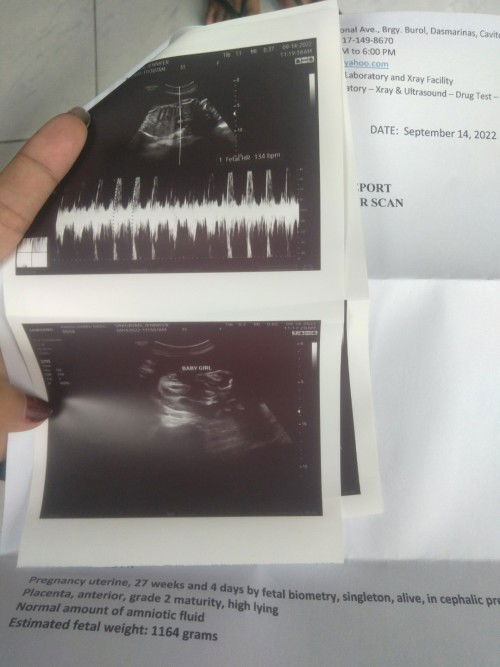

Ultrasound result

Momshie ok po b result ng ultrasound ko po? Ska super galaw na ni baby tlga ays minsan dna mkatulog😔napupuyat ako nababa ung dugo ko#advicepls